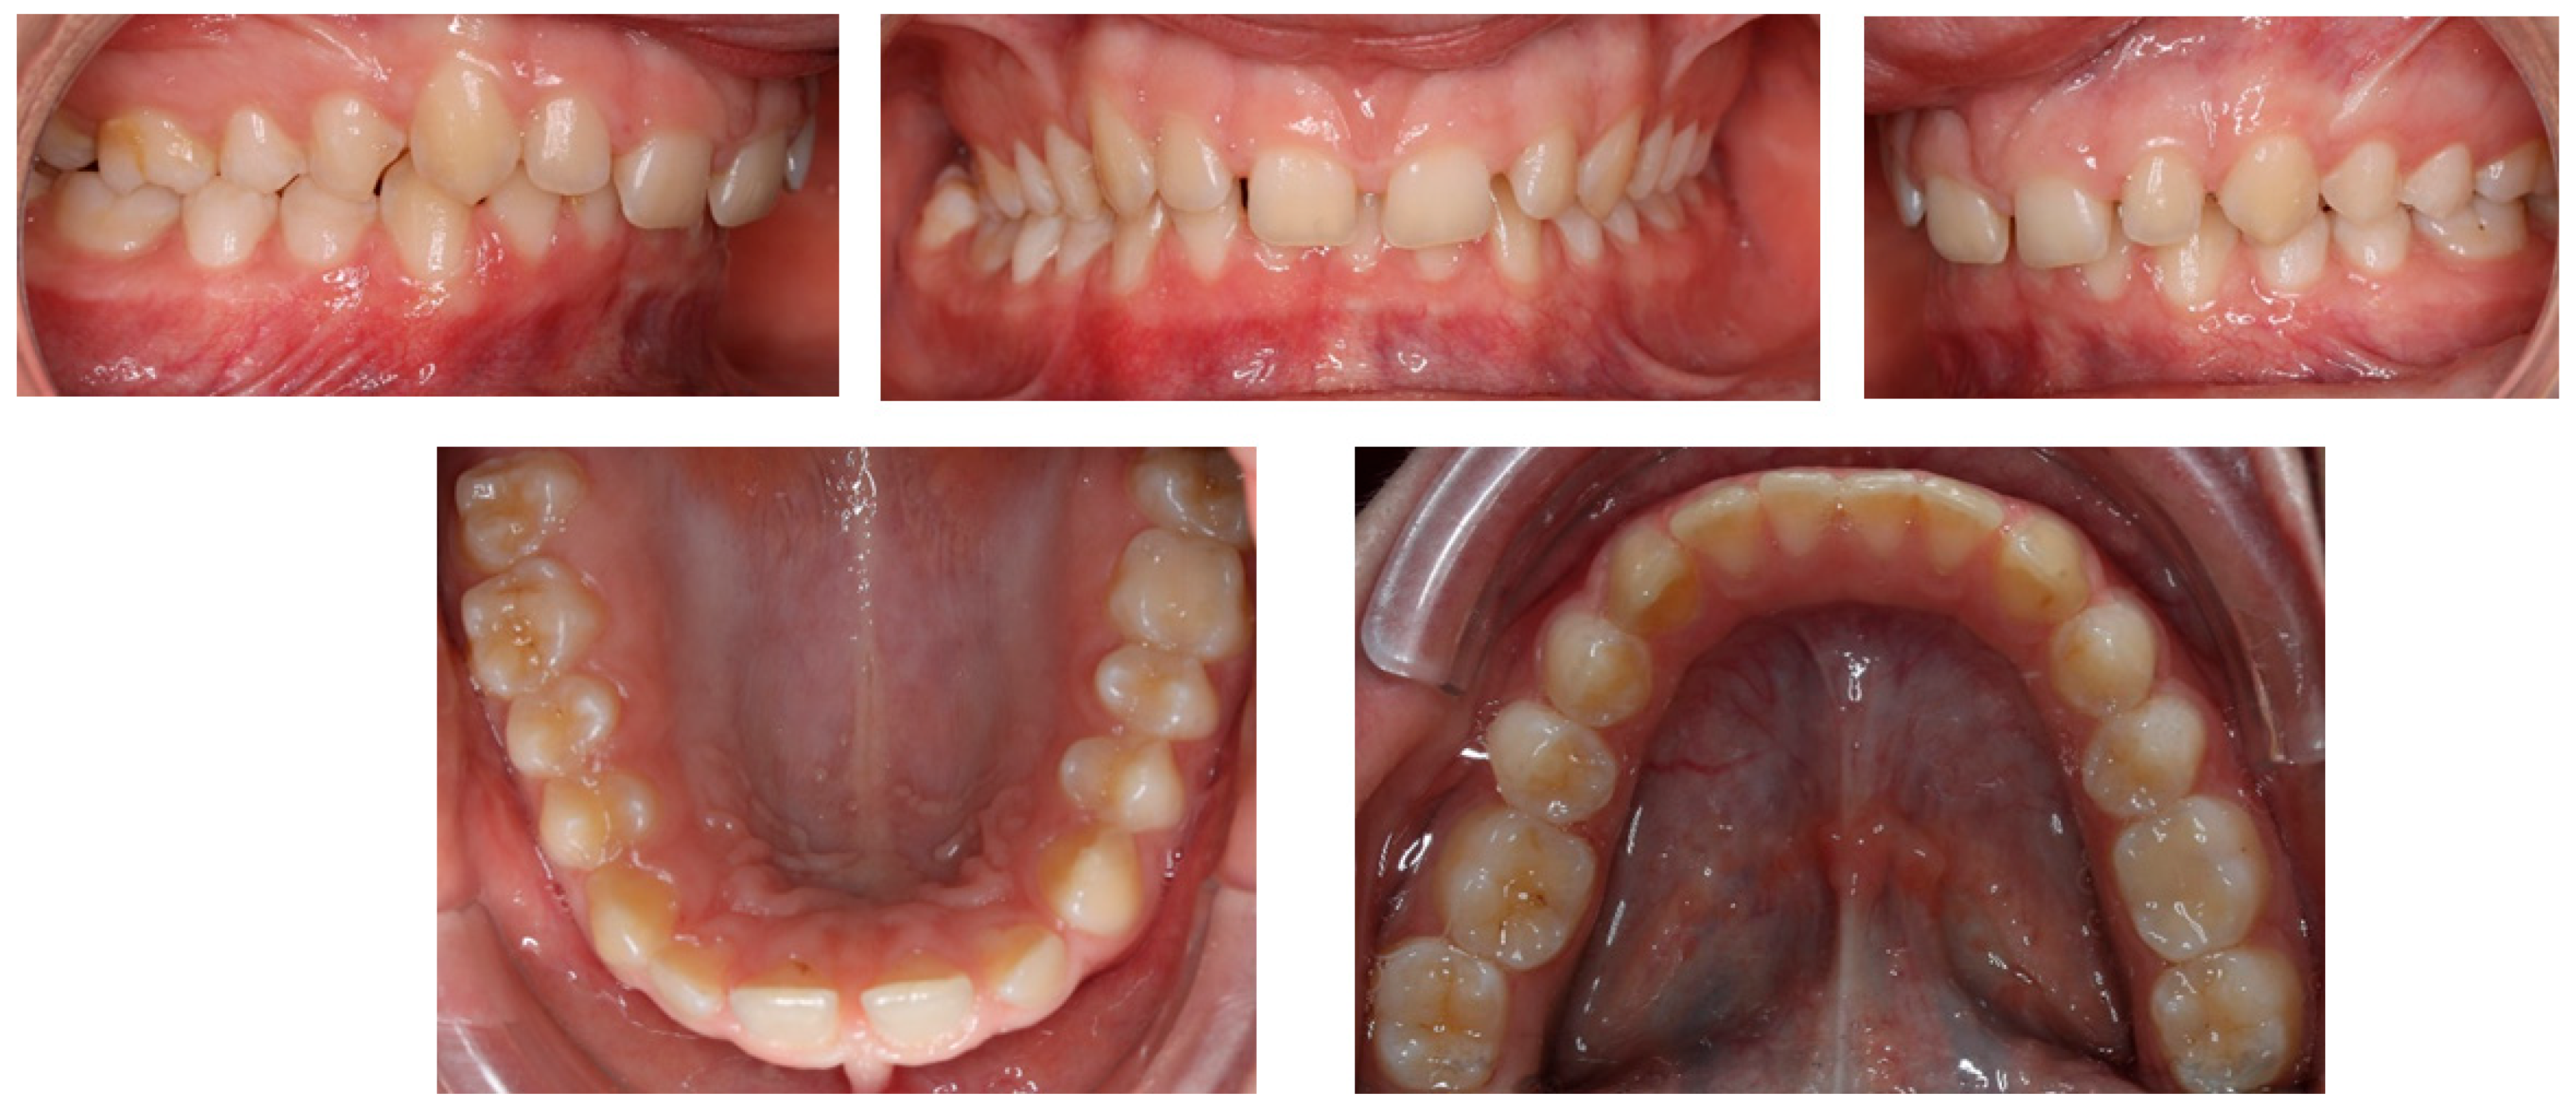

2.1. Diagnosis and Aetiology

2.2. Treatment Objectives

2.3. Treatment Progress